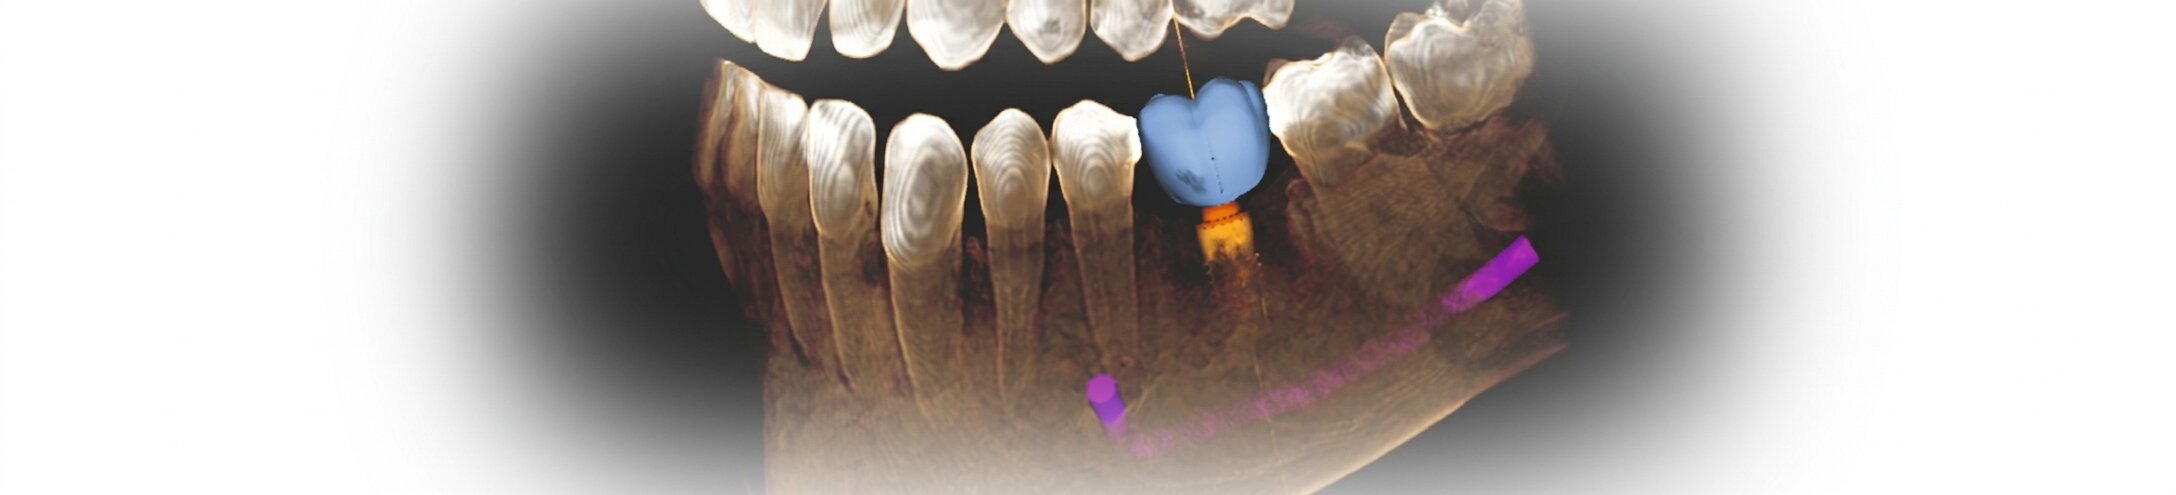

Die perfekte Position des Implantats ist entscheidend für den dauerhaften Behandlungserfolg. Nicht nur die ausreichende Knochensubstanz ist hierfür wichtig. Bei der Positionierung des Implantats gilt es außerdem darauf zu achten, dass keine Wurzeln oder Nerven verletzt werden. Zudem müssen Tiefe und Ausrichtung des Implantats genau stimmen, damit später der Zahnersatz – die Krone, Brücke oder Prothese – exakt angepasst werden kann. Durch die 3D-Planung kann außerdem die Ästhetik bereits vor dem Einsetzen der Implantate exakt vorausgeplant werden.

Der nötige Abstand zu sensiblen Nerven und die optimale Implantattiefe werden bei der computergestützten 3D-Planung exakt berechnet. Eine Software ermöglicht eine dreidimensionale Planung am Bildschirm und bietet beste Voraussetzungen, um das Implantat sicherer und genauer setzen zu können. Dies erfolgt über Schablonen, die auf Grundlage einer individuellen 3D-Planung hergestellt werden.